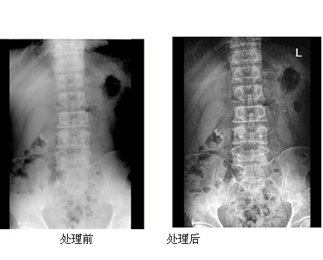

Angell-DR大型X光机工作站

Angell-DR具有更简洁方便优势,重要的是实现高清数字化、专利图像增强技术,使得影像更清晰,便于医生更加方便直观查看病情,有利于病人的病情诊断。